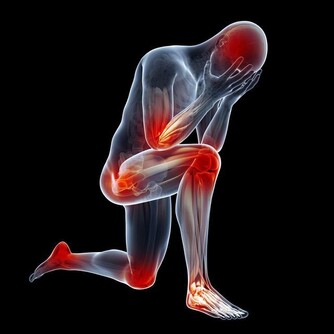

類似姚女士這樣,因為肩背疼查出其它疾病的患者不算少,

他提醒,天氣轉冷,肩背疼痛的患者也多了起來,

然而肩背痛不一定就是肩周炎或是頸椎病,它可能提示其它疾病:

3.多數膽囊炎的首發症狀是背疼,或是右肩、右肩胛下隱痛。

要還有噁心、腹脹、反酸、胃部灼燒感等消化不良症狀,別忘了去醫院做個彩超檢查一下膽囊。

4.患有高血壓的中老年人,突然覺得背疼,或是前胸、腹部疼痛難忍,

像是身體被刀割或是撕裂了似的,有可能是主動脈夾層,一定要儘快就醫。

如果搶救不及時,約四成患者可能會在24小時內死亡。

5.心絞痛、心肌梗死,也會放射至後背、左肩等部位,冠心病患者要是突然覺得肩背疼要小心。